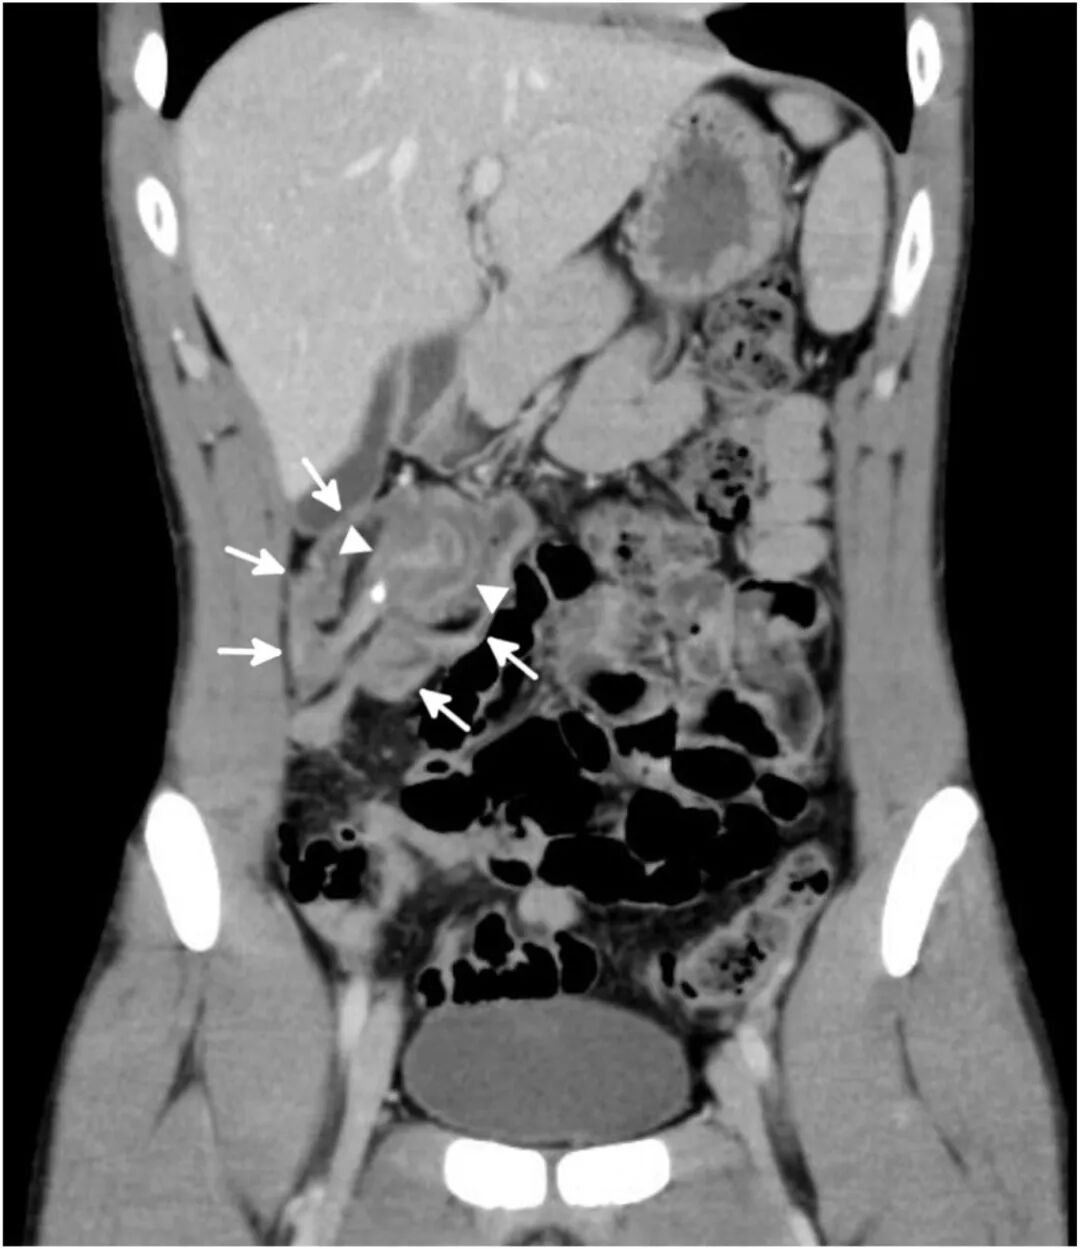

体格检查发现右下腹有明显压痛。患者生命体征在正常范围内,但实验室检查显示白细胞增多(白细胞计数 10100/μL,中性粒细胞占85%)。计算机断层扫描(CT)显示盲肠内陷升结肠引起的阑尾肠套叠(图1、2)。该套叠的头部为一个增大的阑尾,其中包含一枚阑尾粪石。

图1 腹部及

图2 腹部及盆腔CT检查(冠状位)显示盲肠(箭标所示)套入升结肠(箭头所示)。